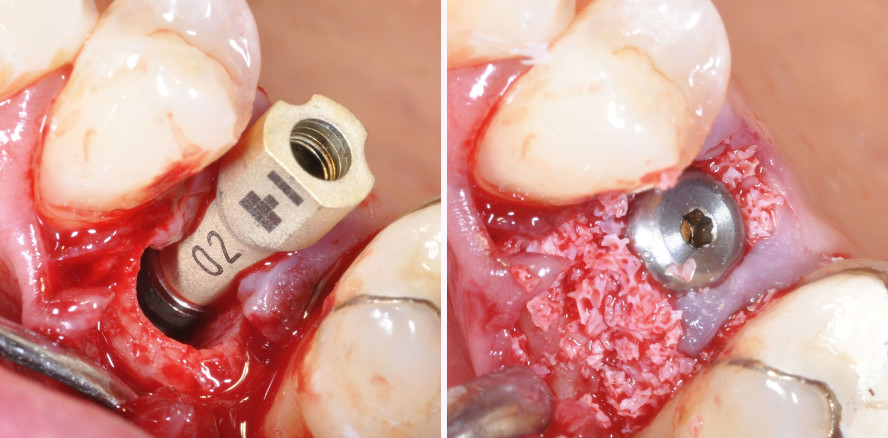

Es erfolgte ein diagnostisches Röntgenbild sowie ein digitaler Scan von Oberkiefer und Unterkiefer und der Bisssituation (Primescan, Dentsply Sirona; Abb. 3 und 4). Es wurde ein Implantat 3,8 x 13 mm (Camlog SCREW-LINE, BioHorizons® Camlog) Regio 15 nach schonender Zahnextraktion inseriert (Abb. 5–7). Nach Zahnextraktion erfolgte ein erneuter Scan der vorhandenen Extraktionsalveole im Sinne einer „Biokopie“. Die Implantatposition wurde mithilfe eines Scanbodys (3Shape) übertragen (Primescan, Dentsply Sirona; Abb. 8 und 9).

Die Scans prä und post extractionem wurden mit dem Scanbodyscan digital gematcht (Abb. 10). Die Schulter des Implantats wurde ca. 3 mm unter der bukkalen Knochenlamelle platziert (Abb. 7). Der Verschluss erfolgte mit einem Gingivaformer PS, wide body (BioHorizons® Camlog) in 4 mm Höhe, der mit einer Verschlussnaht und Membran überdeckt wurde (Abb. 11). Dieses Verfahren hat sich bewährt, um nach der Einheilzeit lediglich den konfektionierten Gingivaformer gegen das individuelle Abutment auszutauschen. Da sich in der Zeit ein stabiles und dickes Weichgewebe gebildet hat, ist oft lediglich eine minimale Aufweitung für das individuelle Abutment nötig. In vielen Fällen kann hierauf verzichtet werden und der Gingivaformer wird ohne Aufweitung gegen das Abutment ausgetauscht. Der Kieferknochen wurde mit Eigenknochenspänen, die mittels Safescraper3 gewonnen wurden, und einem Knochenersatzmaterial (MinerOss XP, BioHorizons® Camlog) aufgebaut sowie mit einer Membran (Memlock RCM®, BioHorizons® Camlog) zum Schutz vor einwachsendem Weichgewebe bedeckt (Abb. 12–15).4, 5